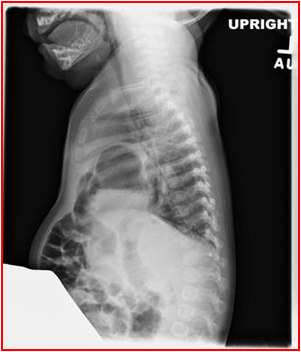

产后诊断Diagnosis after birth

胸腹部正侧位摄片:

◇ 可见患侧胸腔内有典型的充气胃和肠曲,并向腹部延续现象。

◇ 病变侧看不到正常膈肌 形态。

◇ 腹部气体影减少。